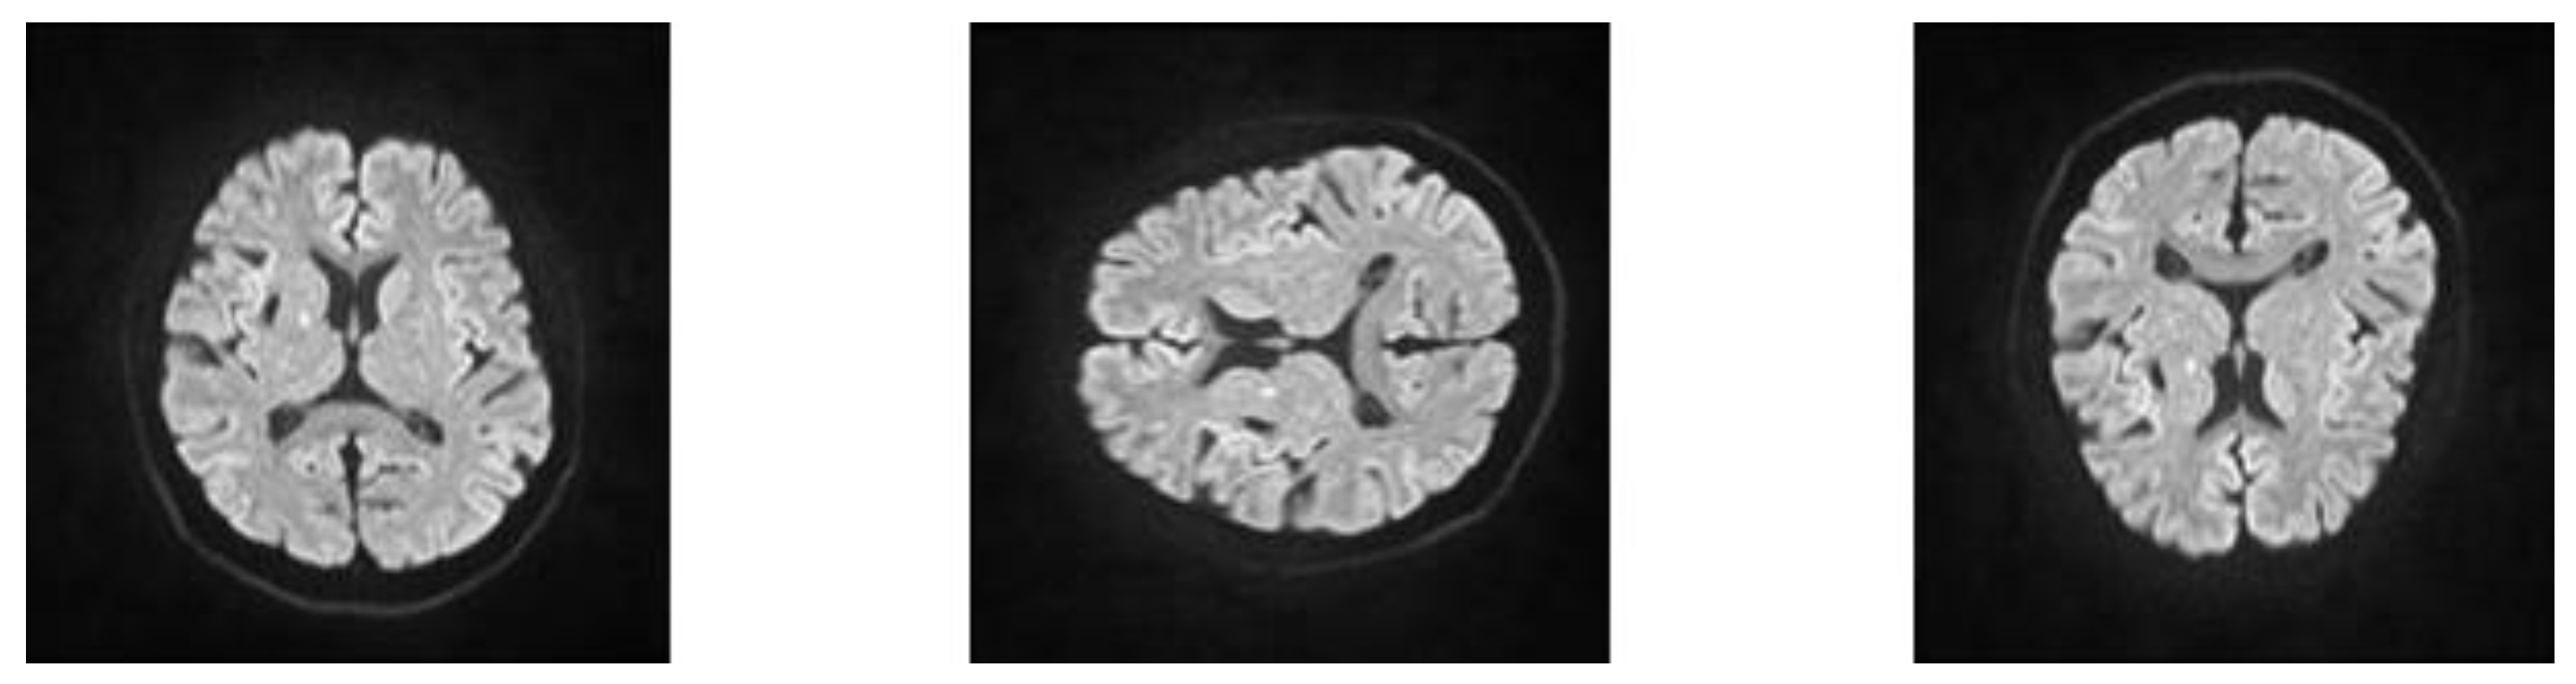

2.2. Imaging Acquisition